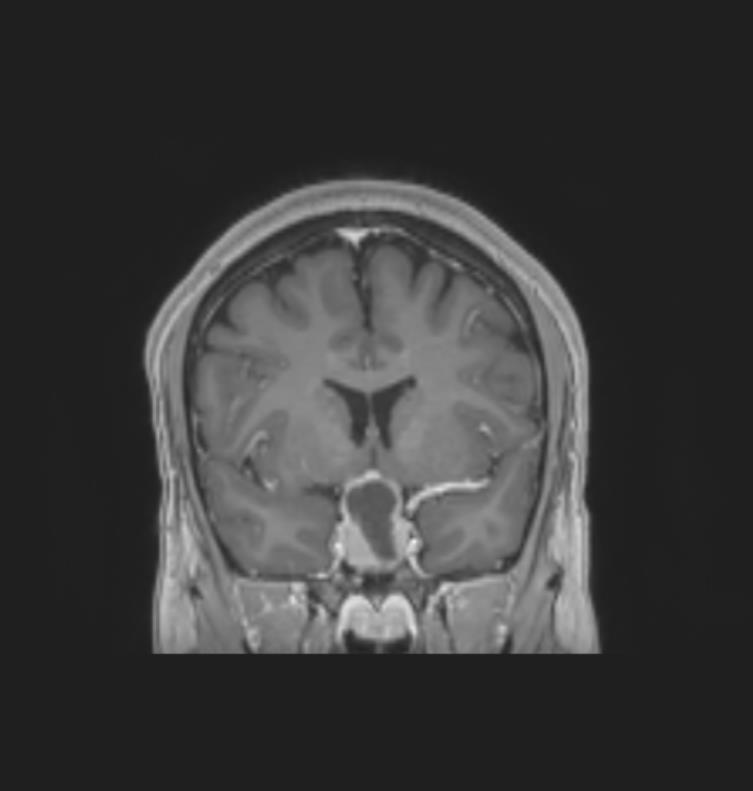

Le patient bénéficie également d’une imagerie par résonance magnétique (IRM) cérébrale devant un doute sur le scanner. Voici deux coupes (figures 2 et 3) :

Figure 3 (source : G. Kielwasser)

Question 10 - Les réponses justes à propos de ces coupes sont les suivantes :

Figure 3 bis (source : G. Kielwasser)

Sur cette coupe sagittale en T1 avec injection de gadolinium (figure 3 bis), on observe les mêmes structures que sur la coupe précédente, avec la flèche jaune pointant le macroadénome hypophysaire hémorragique et la ligne rouge représentant la limite virtuelle de la loge pituitaire. La flèche verte pointe le chiasma optique comprimé par la masse.